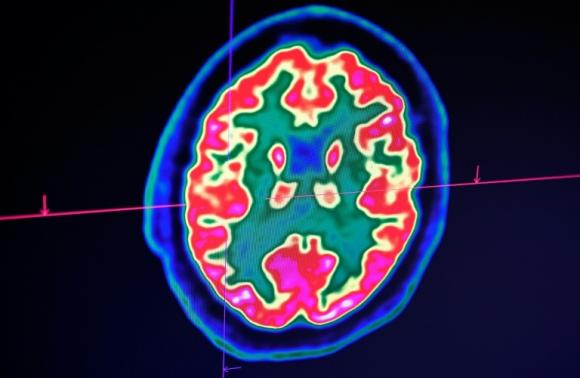

Ảnh chụp não người bằng máy chụp cắt lớp positron (PET). Ảnh: AFP.

Nghiên cứu đăng trên Tạp chí Hiệp hội Y khoa Mỹ (JAMA) tuần trước cho thấy 36,4% trong số 214 bệnh nhân Trung Quốc được khảo sát có dấu hiệu về thần kinh, từ mất khứu giác đến đau dây thần kinh, co giật và tai biến mạch máu não.

Nghiên cứu khác trên Tạp chí Y khoa New England tuần này trên 58 bệnh nhân ở Strasbourg, Pháp, cho thấy trên một nửa bị lẫn hoặc bị kích động, và hình chụp não có dấu hiệu viêm.

“Bạn vẫn nghe đó là căn bệnh làm khó thở, nhưng nó cũng ảnh hưởng đến bộ phận chúng ta quan tâm nhất, đó là não”, S Andrew Josephson, Trưởng khoa thần kinh tại Đại học California, San Francisco nói với AFP.